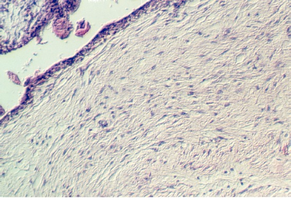

Slide 90 shows uterine epithelium undergoing the decidual reaction. The area is shown in the photos below. Pieces of placenta might be seen attached to the outer edges.

The fertilized ovum divides as it moves down the oviduct. By the fourth day, a central cavity appears and it is called the blastocyst. This attaches to the uterine endometrium which is in the secretory phase. After the blastocyst attaches, the endometrium undergoes the "Decidual reaction" The stellate stromal cells enlarge, and become polyhedral. They contain glycogen and lipid and presumably provide a source of nourishment for the implanting embryo.